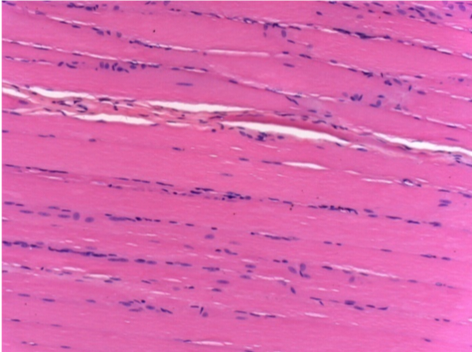

Complete Restitutio ad integrum after 7 months

L :Control 50xD210

R50X-D210

7 months (D210)after Endopeel IM Injection 0.1ml in the right pretibial muscle.